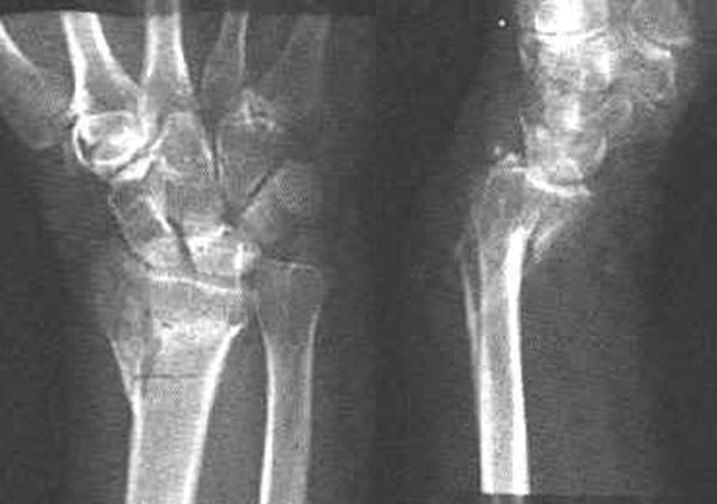

Colles骨折

桡骨远端骨折

骨折向掌侧成角

远折端向背侧移位

Smith骨折

正常腕关节

月骨周围脱位